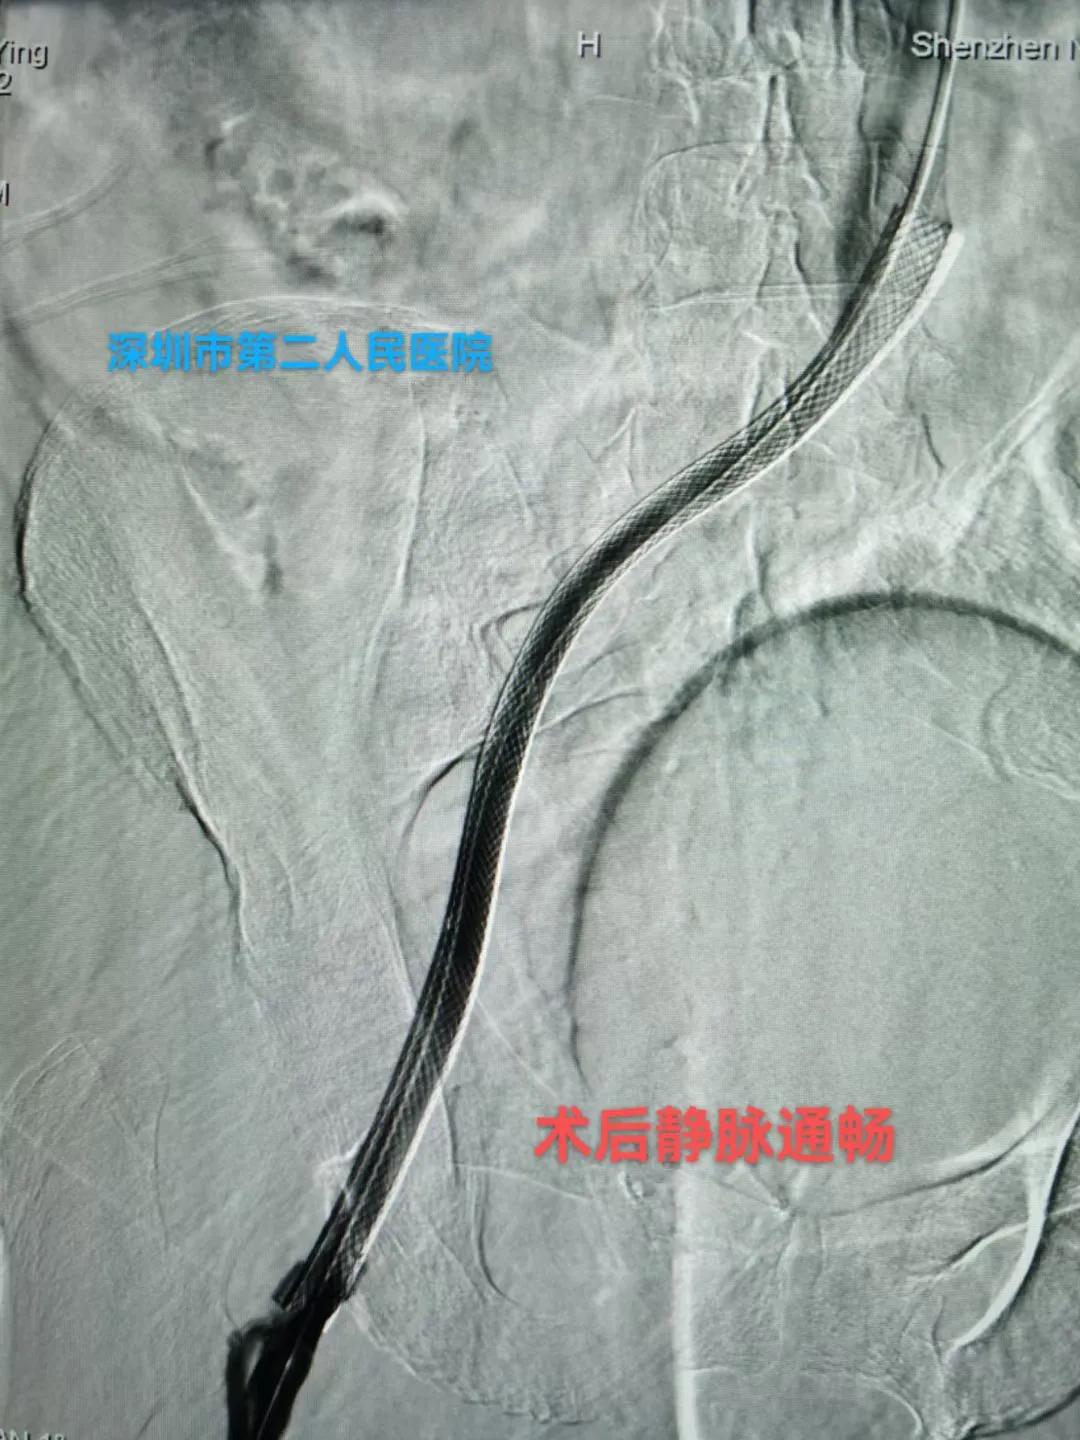

答:这个就需要根据患者自身情况制定个性化治疗策略,主要策略为:①保守抗凝治疗:②系统溶栓治疗;③导管接触性溶栓治疗;④机械性血栓清楚治疗;⑤必要时球囊扩张和支架植入治疗;⑥急危重症病人需切开取栓治疗等。

支架后髂静脉通畅

支架植入后血流通畅